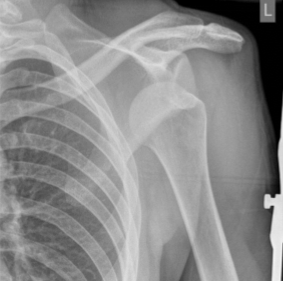

shoulder - anterior dislocation

shoulder - posterior dislocation